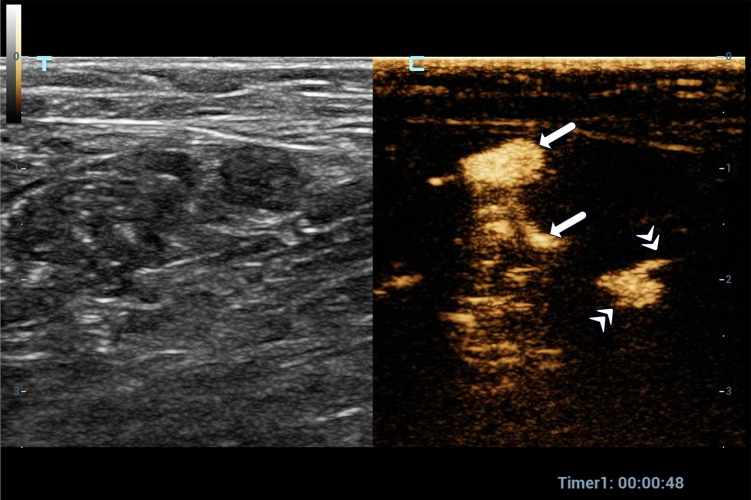

Methods: A total of 176 patients with breast cancer who underwent preoperative SLN-CEUS to trace axillary sentinel lymph nodes were included. The positive result of SLN-CEUS was defined as both lymphatic vessels and SLN visible. The negative result was defined as the visible lymphatic vessels but the SLNs invisible, and neither lymphatic vessel nor SLNs invisible. Clinical features, histopathology, ultrasound features and doses of contrast agents were analyzed between the positive and negative groups.

Abstract Image